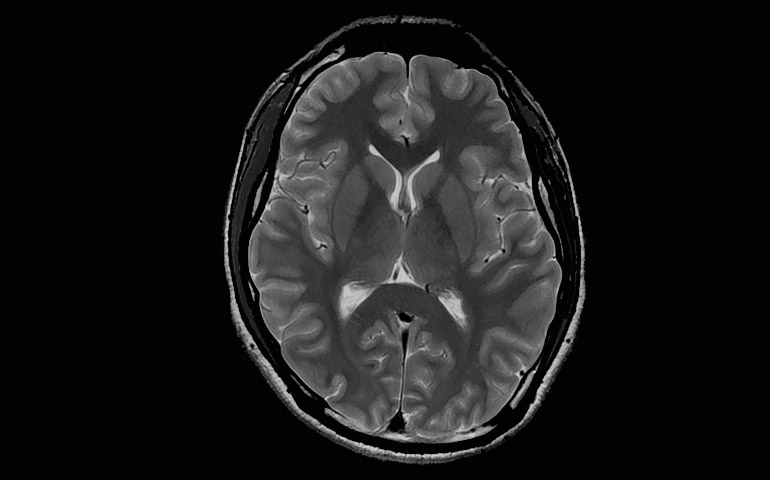

Siendo referentes en tecnología y en otorgar apoyo clínico en diagnósticos a través de imágenes, centro de diagnóstico San Lorenzo recibe en sus instalaciones un nuevo resonador magnético de 3 Teslas, lo que facilitará a médicos especialistas contar con tecnología en imagen médica de alta calidad en la zona centro sur, permitiendo detectar oportunamente enfermedades de alta complejidad, como también la posibilidad de obtener información más exacta sobre diferentes patologías en pacientes que padezcan alguna enfermedad neurológica, cardiológica, vascular, y oncológica entre otras. Este equipo siendo una tecnología 100% digital, busca principalmente apoyar en su labor a médicos especialistas que requieran profundizar sus estudios clínicos y obtener información más certera para abordar casos de mayor complejidad.

Siendo primeros y únicos en traer esta avanzada tecnología en imagenología médica, la llegada de este nuevo resonador magnético de 3 teslas a la región de O'Higgins generará la posibilidad de optar a una amplia opciones de nuevos exámenes sin variar su valor para que pueda acceder la comunidad, permitiendo captar imágenes con mayor resolución anatómica e identificar con mayor detalle el estado de patologías de alta complejidad en pacientes, contribuyendo a médicos a una mejor planificación en los tratamientos futuros que se apliquen según cada caso. Otra de sus características, es que gracias a la amplitud del diámetro del túnel que posee este moderno equipo permitirá el estudio de pacientes obesos, ancianos, embarazadas, y niños. Reduciendo el nivel de estrés y la sensación de claustrofobia para quienes puedan presentar este tipo de síntomas en los procedimientos. Lo que significa mayor seguridad, mejores resultados, y más comodidad al momento de realizar sus exámenes.